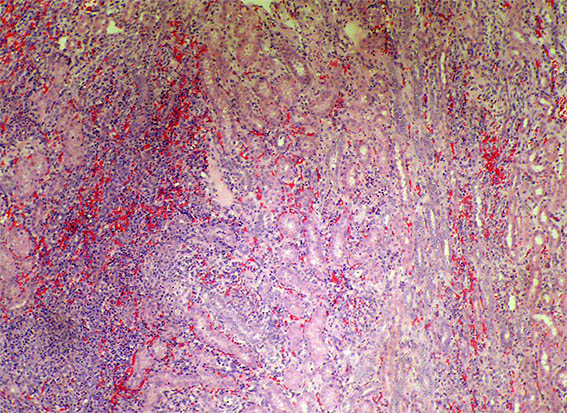

Figure 4. H&E, X100. A transition zone between the upper pole lesion (left) and normal parenchyma (right).